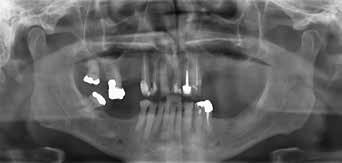

Der Patient wurde im Zuge der Tumornachsorge wieder an der Universitätszahnklinik Wien vorstellig. Am Beginn der prothetischen Fallplanung wurden montierte Situationsmodelle erstellt und ein aktueller Röntgenstatus erhoben. Intraoral bestätigte sich, dass der resezierte Bereich mittels eines Zungentransplantates gedeckt wurde.

Abb. 24: Kontrollpanoramaröntgen nach erfolgter Eingliederung